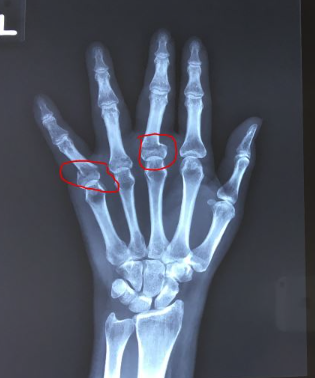

손가락 골절 깁스, 의료용 손가락 보호대 후기

손가락이 골절되거나 손가락 인대가 늘어 났을 경우 손가락에 압통과 부종이 발생하고 마디에 멍이들어 푸...